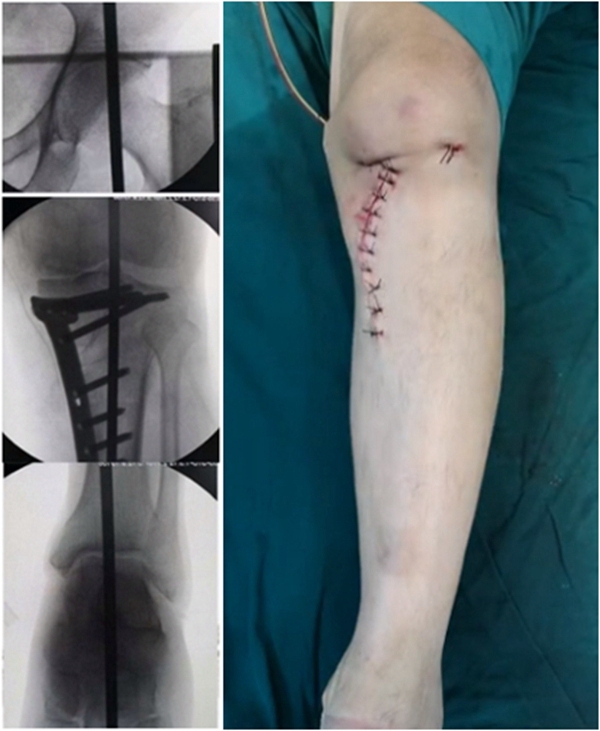

术后检查证实达到了术前预期的手术效果,关节线达到了平行,半脱位得到矫正,同时关节线和地面水平。病人行走达到了理想的效果。

术后X线

患者术后4个月截骨愈合,膝关节稳定维持得非常好。

术后4个月